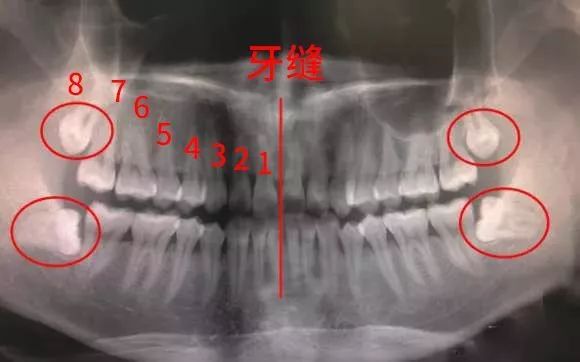

一般最多可长4颗,分别在上下两排牙齿的左右最里面那一颗。具体发育几颗因人而异,有些人4颗都长齐了。

什么叫做“叛逆少年型”?看看下面的图片感受下——

看到没?

这些都是走了歪路的“叛逆少年”